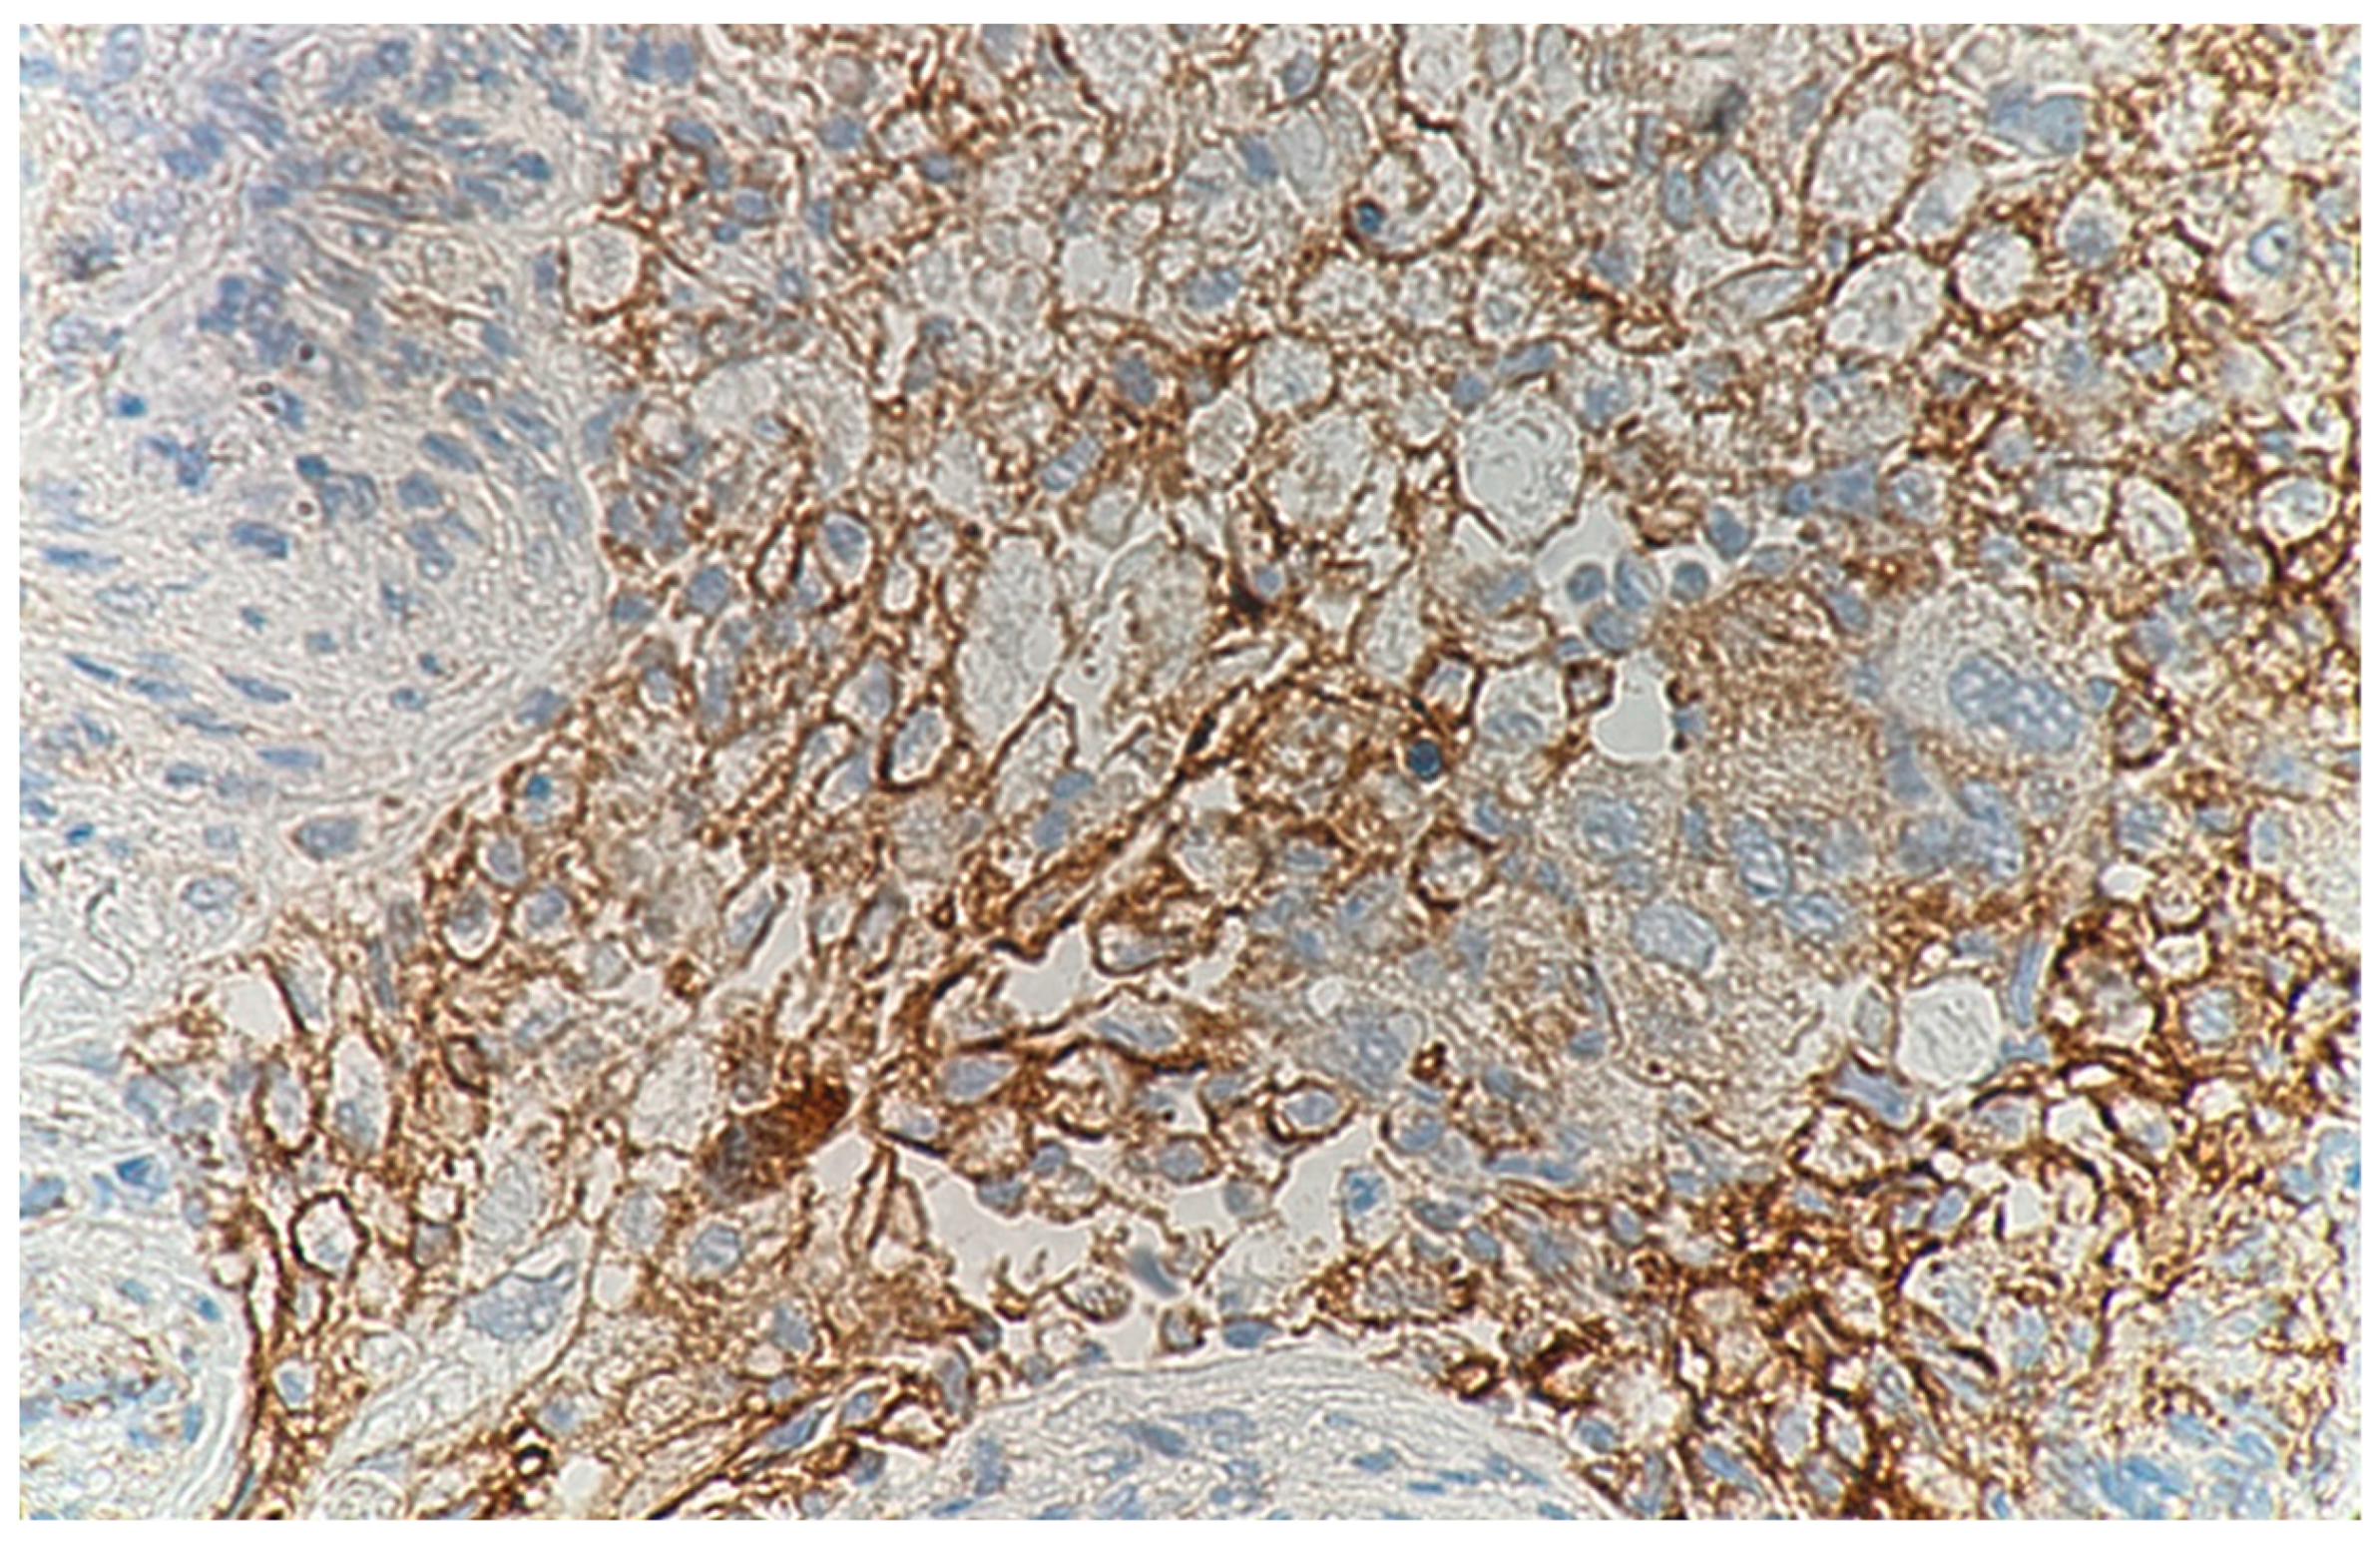

Programmed Death-Ligand 1-Positive Squamous Cell Carcinoma Spontaneously Regressed after Percutaneous Needle Biopsy

2. Case Report